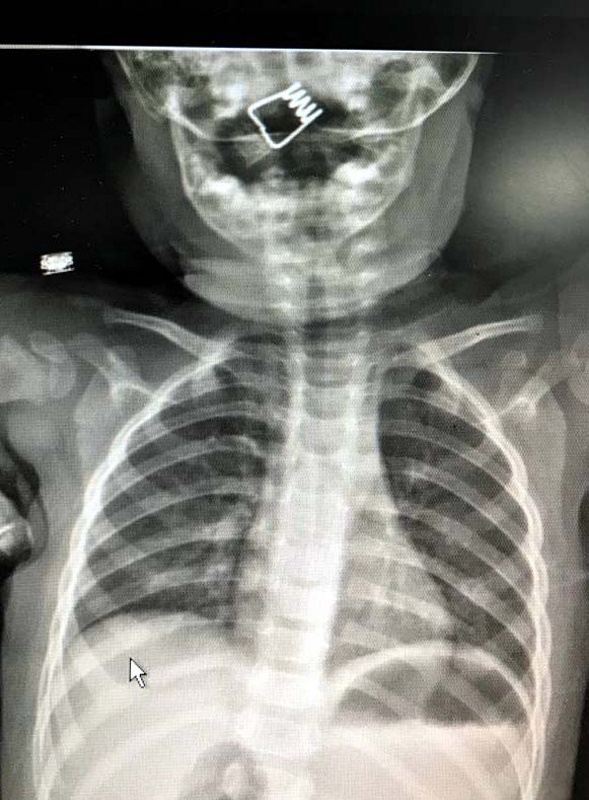

Nevşehir Devlet Hastanesi Acil Polikliniği'ne getirilen bebeği, Acil Nöbetçi doktoru Mustafa Alpaslan muayene ederek gerekli tetkikleri yaptı. Çekilen röntgen filmlerinde mandal yayının lokalizasyonu ve durumu belirlendi. Daha sonra, KBB Uzmanı Op. Dr. Ahmet Cevatzade tarafından yapılan başarılı ameliyat sonucunda bebeğin genzine saplanan mandal yayı çıkartıldı.